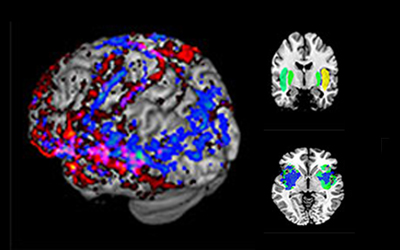

Brain Area Behaves Like an Internet Router

December 2, 2022

The brain’s claustrum receives, amplifies, and broadcasts an ‘internet network’ required to complete complex cognitive tasks.